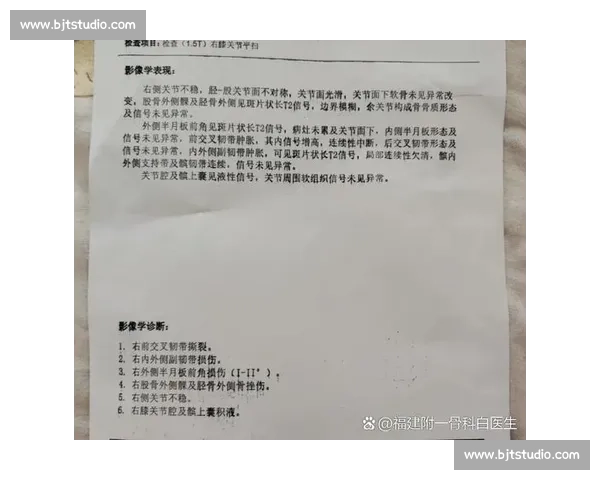

针对运动损伤提供康复方案,包括按摩、理疗、运动机能恢复等专业医疗级服务。